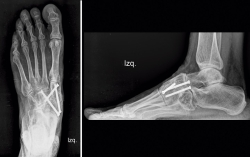

Se ha realizado una revisión a los 3 años, sigue asintomática y hace vida normal. En el estudio radiológico de control (Figura 7) vemos la consolidación y remodelación ósea y clínicamente la tumoración medial ha desaparecido (Figura 8).

Figura 7. Estudio radiológico a los 3 años.